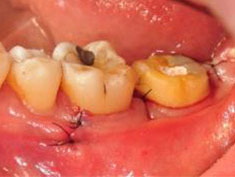

牙周初診時患者之口內觀。口內明顯牙菌斑及牙結石堆積。全口嚴重牙齦紅腫。治療前X光片。#37的近心側有較深的骨內缺損,剩餘齒槽骨高度只有20%。

第一階段牙周基本治療後,牙齦發炎狀況明顯獲得改善。